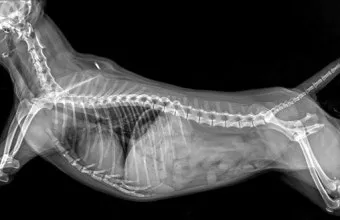

교통사고나 높은 곳에서 떨어졌을 때 발생하는 외상성 복막염도 무시할 수 없어요. 복부에 강한 충격이 가해지면 내장 기관이 파열되거나 혈관이 터지면서 복강 내 출혈이 시작되거든요.

이때는 출혈성 복막염이 발생하는데, 혈액 자체가 복막을 자극해서 염증을 일으켜요. 특히 비장이나 간 같은 혈관이 풍부한 장기가 손상되면 대량 출혈로 이어질 수 있어서 정말 위험해요.